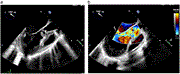

Massive hemoptysis as a sole presentation of left atrial myxoma

Narmeen Giacaman and others

Journal of Surgical Case Reports, Volume 2023, Issue 5, May 2023, rjad301, https://doi.org/10.1093/jscr/rjad301